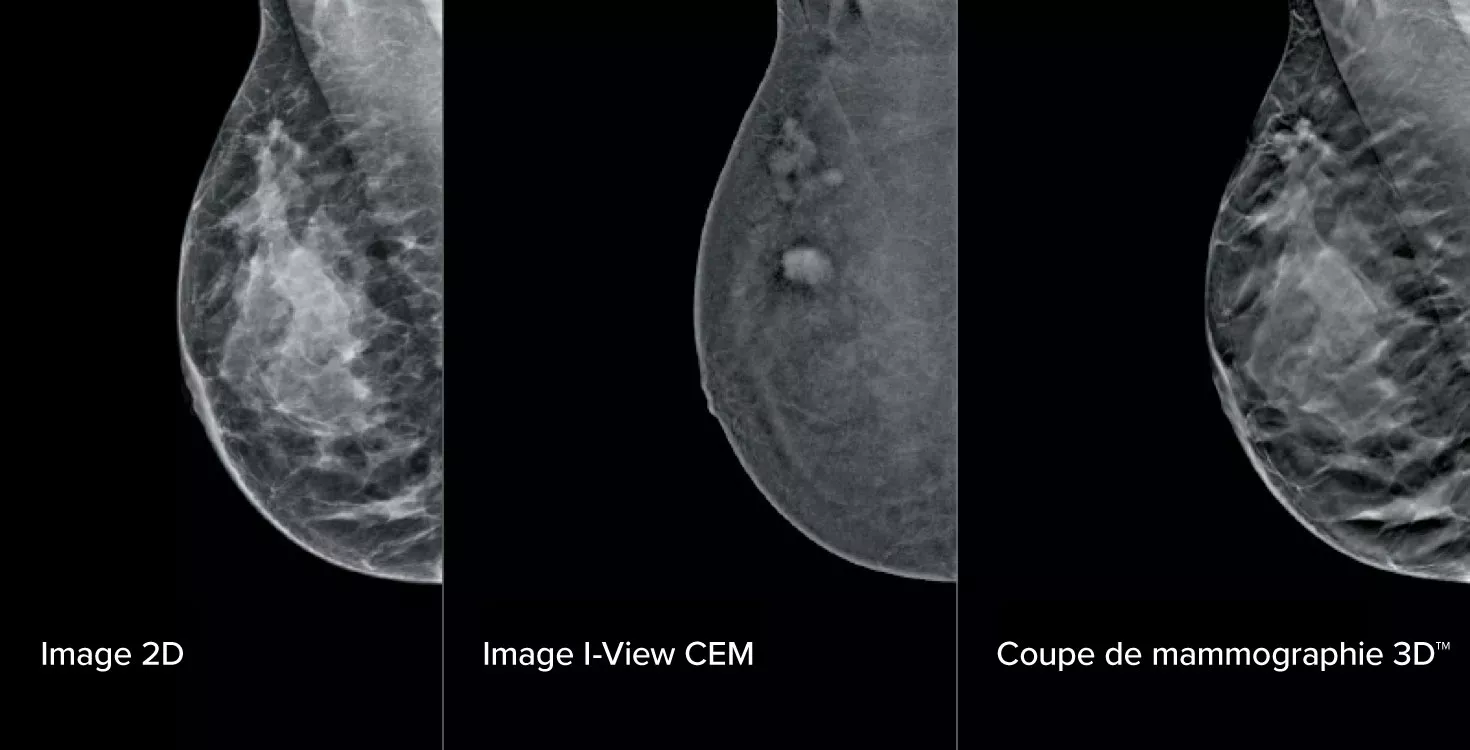

La mammographie avec rehaussement de contraste (CEM), qui consiste en un examen du sein à l’aide d’un produit de contraste iodé pour révéler les zones où la vascularisation est plus importante, peut aider à mettre en évidence les lésions suspectes. Le logiciel I-View permet d’associer la puissance de la CEM aux images 2D et de tomosynthèse lors d’une seule compression pour fournir une imagerie anatomique et fonctionnelle en un seul examen.1

Ce logiciel permet d’obtenir des informations anatomiques et fonctionnelles en un seul examen en tirant parti de notre capacité à fournir des images 2D, de contraste et de tomosynthèse en une seule compression.1